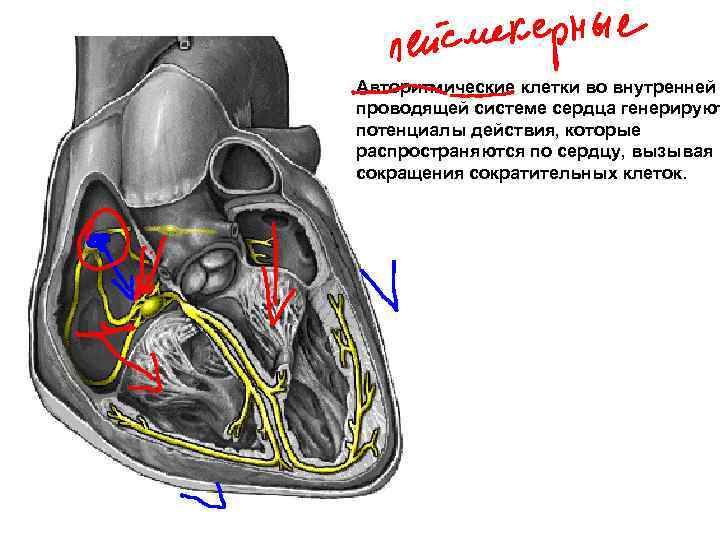

Авторитмические клетки во внутренней проводящей системе сердца генерируют потенциалы действия, которые распространяются по сердцу, вызывая сокращения сократительных клеток.

Авторитмические клетки во внутренней проводящей системе сердца генерируют потенциалы действия, которые распространяются по сердцу, вызывая сокращения сократительных клеток.

действия Направление потенциала Сино-атриальный узел Межузловые волокна Атрио-вентрикулярный узел Пучок Гиса Ножки пучка Волокна Пуркинье

действия Направление потенциала Сино-атриальный узел Межузловые волокна Атрио-вентрикулярный узел Пучок Гиса Ножки пучка Волокна Пуркинье